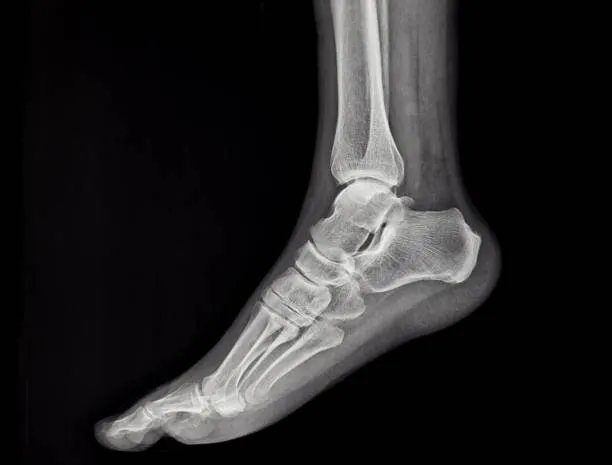

The AP View of the Foot, also known as the Dorsoplantar (DP) View, is a standard radiographic projection used to evaluate the overall anatomy of the foot, including the phalanges, metatarsals, tarsal bones, and midfoot joints. In this view, the patient is positioned either standing or supine, with the foot flat on the image receptor and the X-ray beam angled 10–15° cephalad (toward the heel), directed at the base of the third metatarsal.

This view provides a clear image of the forefoot and midfoot alignment, joint spaces, and bony structures, making it essential for diagnosing fractures, dislocations, arthritic changes, and congenital deformities. The dorsoplantar view is commonly used in both trauma and orthopedic evaluations of the foot.